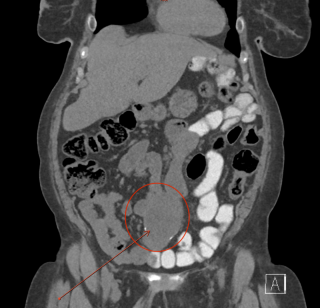

Case presentation

A 45-year-old man with no relevant past medical history presented with acute diffuse abdominal pain following a forceful sneezing episode. Physical examination revealed localized right-sided abdominal tenderness without peritoneal signs. Laboratory tests showed mild leukocytosis with normal inflammatory markers and hemoglobin. Contrast-enhanced computed tomography demonstrated a mesenteric hematoma associated with moderate hemoperitoneum and focal mural hypoenhancement of an ileal loop, without active arterial extravasation (Figure 1). Urgent surgical exploration revealed approximately 500 mL of hemoperitoneum, a large mesenteric hematoma, and an adjacent intestinal pseudodiverticulum (Figures 2-3). Segmental small bowel resection including the diverticulum was performed. Histopathological analysis confirmed fresh mesenteric hemorrhage and pseudodiverticular changes without evidence of malignancy, vasculitis, or vascular malformation. The postoperative course was uneventful, and the patient remained asymptomatic at six-week follow-up.